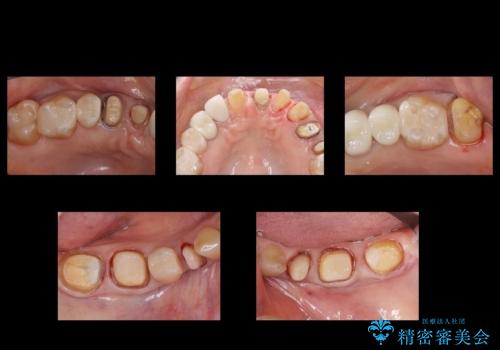

- 銀歯や被せ物のやり替えをご希望で来院。悪いところはすべて治していきたいとのことでした。

根の治療を含めてしっかりやり直しを行いました。

本数も多く、時間はかかりましたが、しっかり通いきっていただきました。